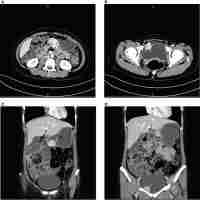

| Abstract | Gastrointestinal stromal tumors (GISTs) are the most common mesenchyme neoplasms of the gastrointestinal tract. Gain-of-function somatic mutations of the KIT or PDGFRA genes represent the most prevalent molecular alterations in GISTs. In Carney–Stratakis dyad, patients portray germline mutations of the succinate dehydrogenase subunits B (SDHB), C (SDHC) and D (SDHD) and develop multifocal GISTs and multicentric paragangliomas (PGLs). We herein report a novel germline SDHB mutation (c.T282A—Ile44Asn) occurring in a 26 years-old patient diagnosed with a spindle cell intermediate risk GIST that did not present KIT/PDGFRA/BRAF gene mutations. Further analyses revealed loss of the wild-type SDHB allele and complete loss of SDHB expression in the tumor tissue. After genetic screening of other family members, we detected in the patient′s mother a SDHB mutation without any clinical/laboratorial evidence of GIST or PGL. Altogether, our findings (germline SDHB mutation with absence of PGL in the index case and of GIST and/or PGL in his mother) raise the possibility that this familiar setting corresponds to an incomplete phenotype of the Carney–Stratakis dyad. |